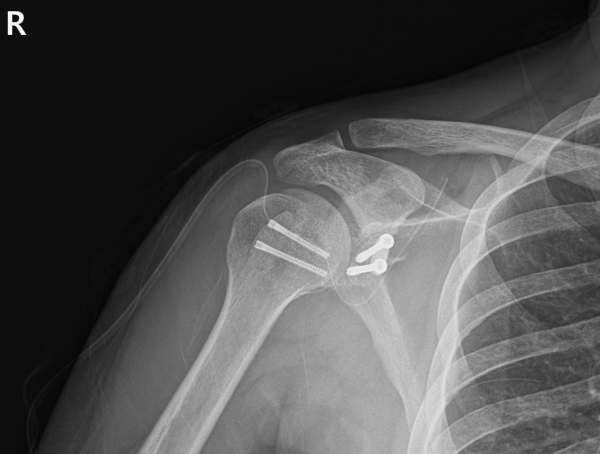

본원에 내원하여 검사를 진행했을 때 다음과 같은 소견을 확인했습니다.

재파열된 전하방 관절와순파열(Bankart) 병변(Recurrent Bankart lesion-재발성 전하방 관절와순파열)

매우 깊고 넓은 상완골두 후외측 골결손(Hill-Sachs) 결손(huge Hill-Sachs lesion-거대 상완골두 후외측 골결손)

상완골두 변형 및 결손

부분층 회전근개 파열

이 정도면 단순한 재탈구 수준을 넘어, 어깨 관절의 안정성이 거의 상실된 상태였습니다.